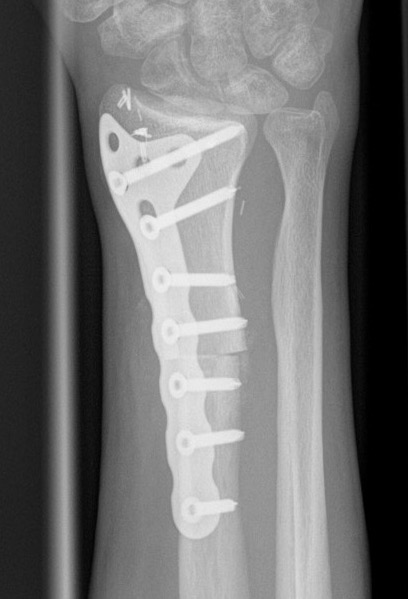

Currettage and Cement +/- local application phenol / liquid nitrogen

Technique

Open approach

- bone window

- remove tissue with curette

- saucerisation with high speed burr

- consider phenol / liquid nitrogen application

- cement (works by thermal necrosis), in addition to structural support

Results

- 354 GCT's treated surgically

- recurrence after curettage 18%